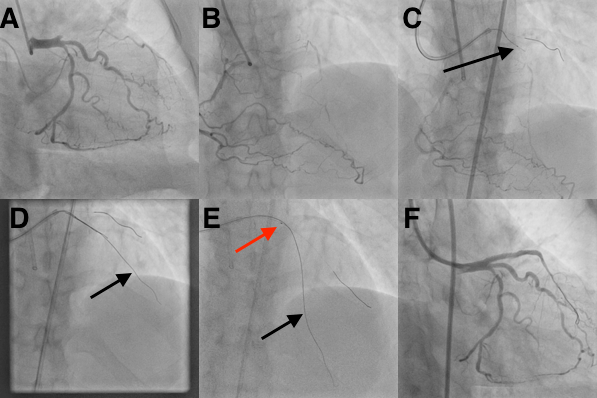

A 50-year-old female patient presented with class III angina for 6 months, positive stress test, and a prior CT angiogram suggestive of 3-vessel disease. Coronary angiogram showed disease of the distal ramus intermedius, proximal circumflex, and calcific chronic total occlusion (CTO) of proximal left anterior descending (LAD) artery (Figure, A & B; Videos 1, 2) with a Japanese (J)-CTO score of 2. She was planned for percutaneous coronary intervention of LAD CTO using a 6-French (F) Judkins right guide catheter from right radial and a 7-F extra-backup catheter from right femoral access.

A Finecross microcatheter (Terumo) and a Fielder XTA wire (Asahi) were used antegrade, however there was subintimal passage of the wire (Figure, C). Parallel wire technique was used, and another Fielder XTA wire was inserted into the first diagonal (D1) branch (Figure, D) near the distal CTO cap but was unable to pierce the distal cap. This wire in D1 was replaced with a balanced middle-weight wire via the microcatheter.

In the absence of a dual lumen microcatheter on shelf, an Export Advance thrombus aspiration catheter (Medtronic) was advanced over D1 wire through the rapid exchange port. Fielder XTA wire was introduced through the over-the-wire port, which resulted in successful antegrade crossing of the LAD (Figure, E; Video 3). A 145-cm DOC wire extension was used to remove the thrombus aspiration catheter over the LAD wire followed by routine removal of the monorail segment. The lesion was subsequently dilated with 1 x 10-mm and 2.5 x 15-mm balloons. Intra-vascular ultrasound (IVUS) was used to assess the vessel diameter, and a 2.75 x 38-mm Xience Prime stent (Abbott) was deployed from the ostial to mid LAD and post-dilated with 2.75 x 15-mm and 3.25 x 12-mm non-compliant balloons with good angiographic and IVUS results (Figure, F; Video 4).